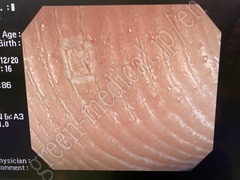

Video Colonoscope PCF-Q240ZI

OLYMPUS

PCF-Q240ZI